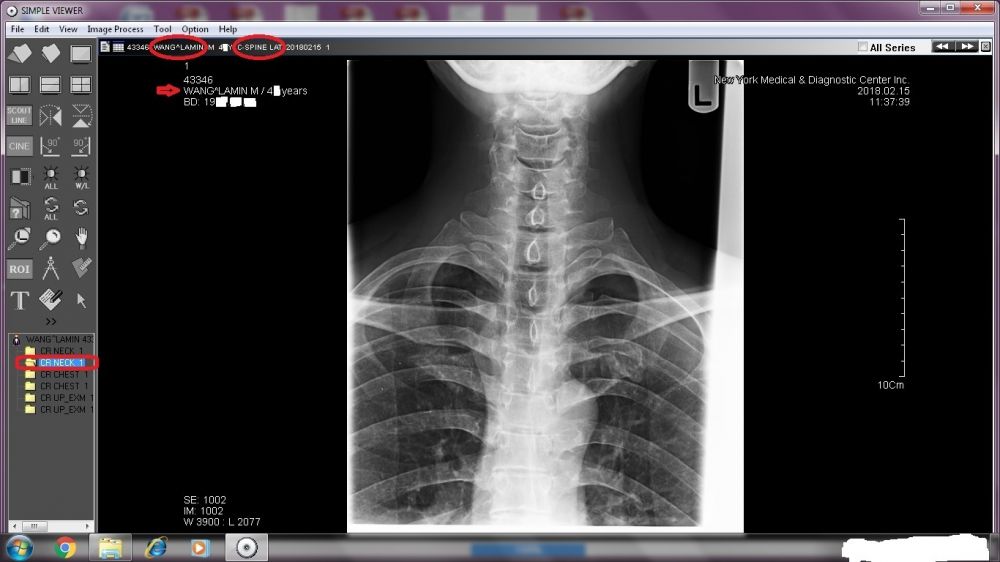

A TREMENDOUS amount needs to be revealed. Right now, I will start with the two sets of X-ray images done by New York Medical & Diagnostic Center (80-46 Kew Gardens Rd, Kew Garden, NY 11415. Tel: (718) 261-1000 ).